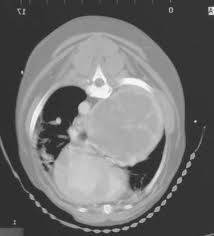

Metastatic lung cancer in dogs refers to tumors that started elsewhere in the body, but metastasized (spread) to the lungs. Most lung tumors are malignant carcinomas (frequently in the form of adenocarnimas). Lung cancer in dogs can be primary or metastatic. Metastatic lung cancer originates in other parts of the body such as a leg bone, the mouth, or the thyroid gland, but has spread to the lung through the bloodstream. The following diagnostics are recommended: Epithelial lung tumors one of the types of tumors are called epithelial lung tumors. The average age of dogs with primary lung tumors is approximately 11 years and the risk of developing lung cancer rises after the age of 13. There are two type of lung cancer diagnosed in dogs. An estimated 158,040 deaths from lung cancer (86,380 in men and 71,660 among women) contrary to the disease in people, lung cancer is very rare in dogs and cats. In the absence of diagnostic testing, it can be challenging to detect lung cancer in dogs. They can be detected on chest radiographs or computed tomography (ct) scanning. Metastatic lung tumors usually present themselves as multiple masses. Some may have a worse prognosis than others.